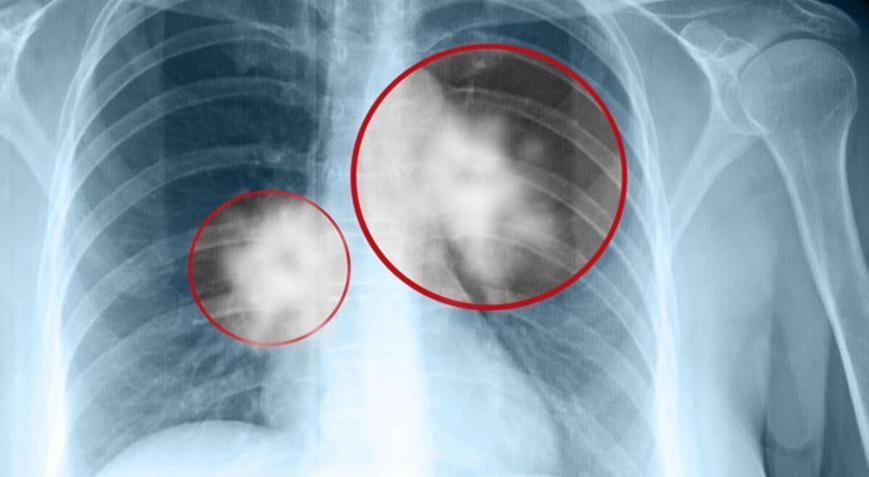

- Крупные новообразования: Флюорография, особенно пленочная, лучше всего "видит" крупные опухоли, как правило, уже на поздних стадиях развития. Если опухоль достигает размера 1 см и более, шансы ее обнаружения значительно возрастают. Рак легких на флюорографии может проявляться как уплотнение (тень), часто с нечеткими, "лучистыми" краями, или как шаровидное образование. Также могут быть заметны изменения в корнях легких или увеличенные лимфатические узлы.

- Периферический рак: Коварство периферического рака легкого, который развивается на периферии легкого, заключается в том, что он может долгое время расти без симптомов и оставаться незаметным на флюорографии, особенно если опухоль небольшого размера (до 5 мм).

- Ранние стадии: Флюорография не является оптимальным методом для выявления рака легких на самых ранних стадиях (например, стадии T1N0M0, когда опухоль очень мала и не дала метастазов). В таких случаях ее информативность значительно ниже. Симптомы рака легких на ранних стадиях часто отсутствуют, что делает его выявление сложным.